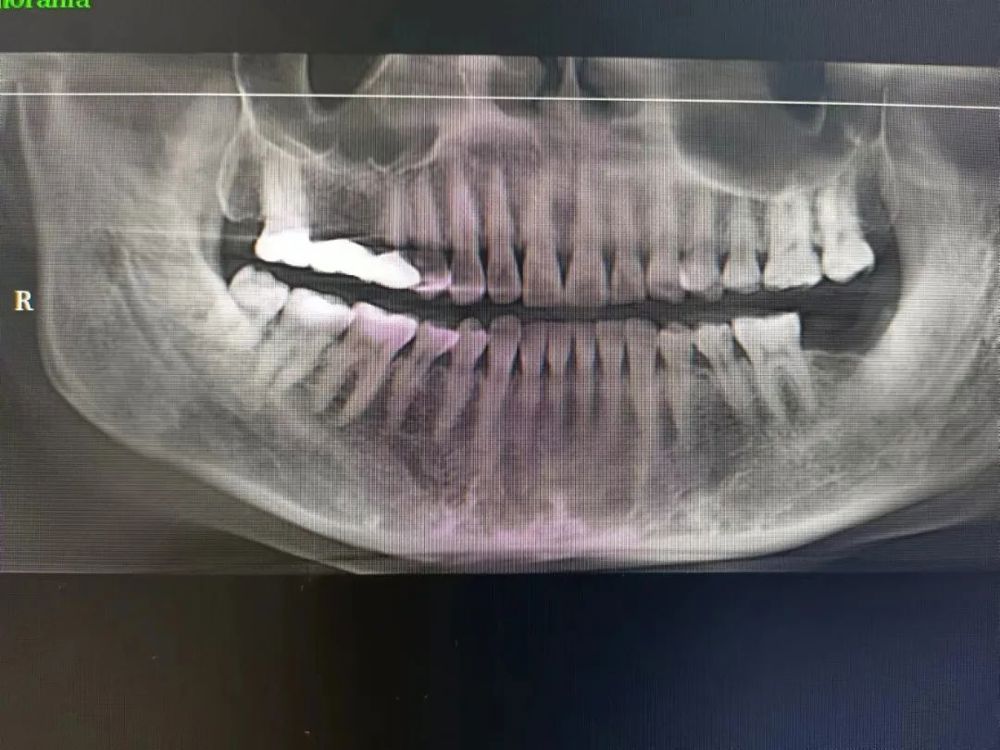

案例一

種植前 種植後